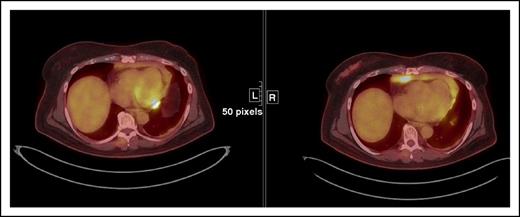

3. Increase in FDG uptake of 1 or more lesion(s) without a concomitant increase in lesion size or number [IR(3)] (Figure 5)

IR(3) showing an increase in FDG uptake in a paracardiac node suggestive of lymphoma without a concomitant increase in size of lesion(s) that meets PD criteria.

While awaiting a better characterization of this phenomenon, we propose that, under the modified response criteria, an increase in FDG avidity of 1 or more lesions suggestive of lymphoma, without a concomitant increase in size of those lesions meeting PD criteria does not constitute PD.